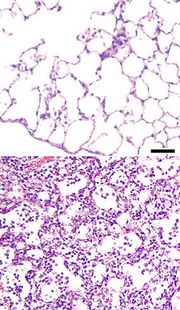

Horní obrázek ukazuje zdravou plíci. Dolní plíci během zápalu plic, kde plicní sklípky jsou plné tekutiny a částic